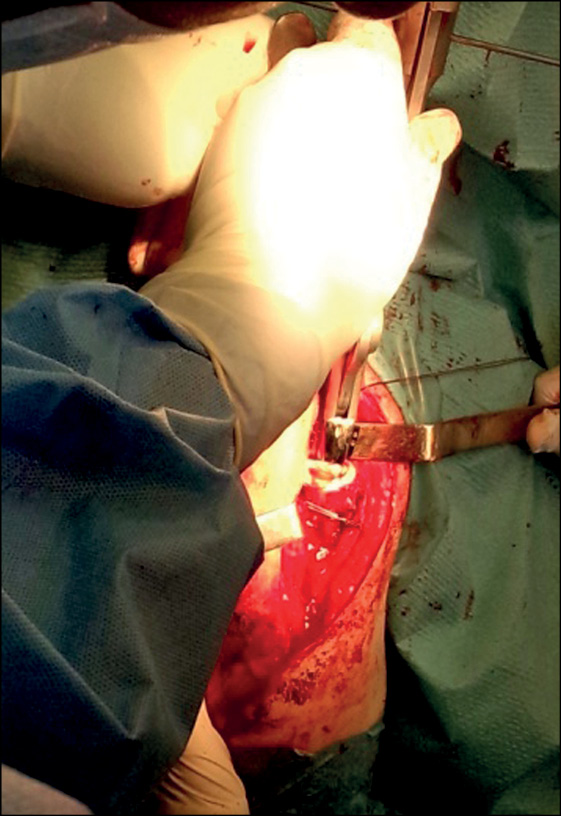

Пациенту с перипротезным переломом диафиза плечевой кости проведена ревизионная операция с целью остеосинтеза диафиза плечевой кости серкляжным способом (рис. 4, 5).

Рис. 4. Ревизионная операция, этап остеосинтеза серкляжным способом перипротезного перелома диафиза плечевой кости

Fig. 4. Revision surgery, osteosynthesis of periprosthetic humerus diaphysis fracture using cerclage technique